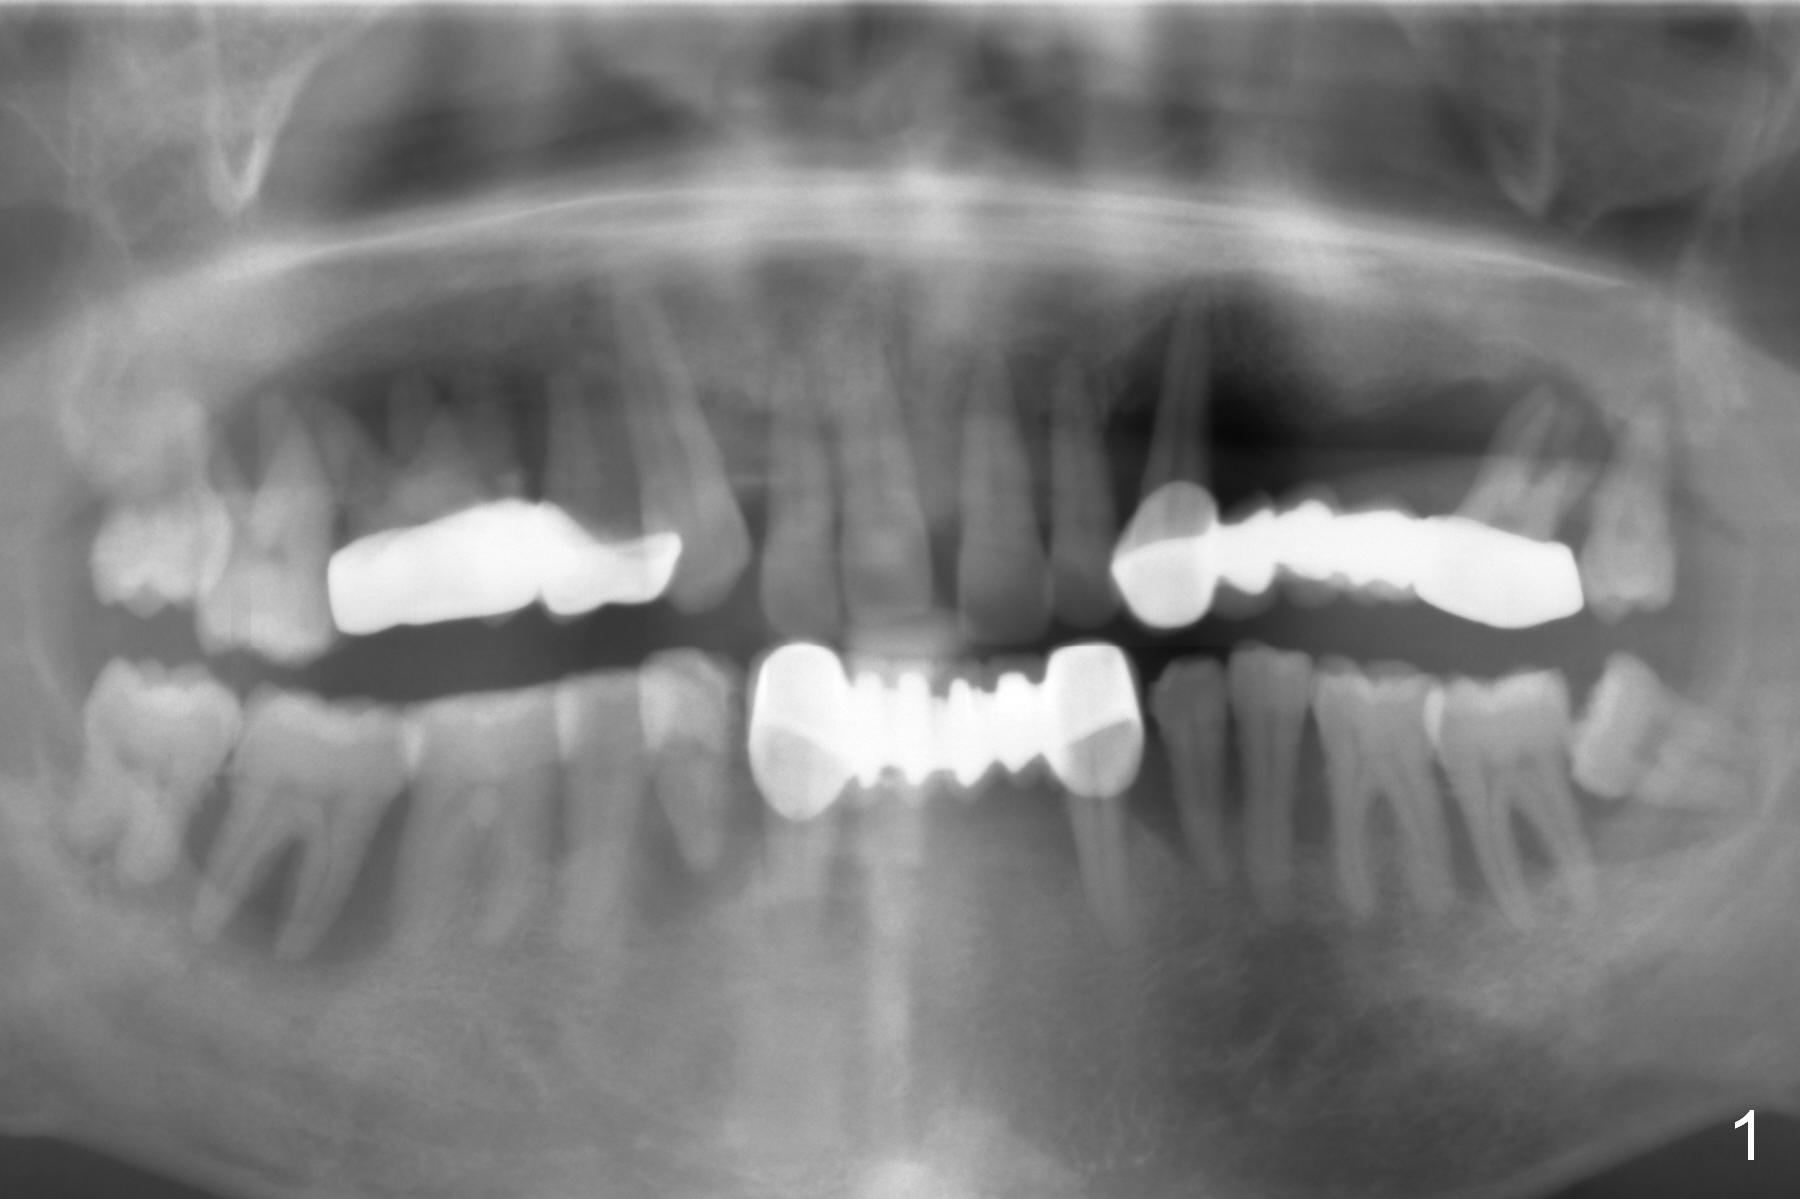

A 45-year-old man has advanced periodontitis and bruxism (sufficient remaining bone height, Fig.1). Full mouth restoration will be done by quadrant with preservation of a few of relatively healthy teeth. The 1st quadrant to be treated will be the upper left (Fig.2). The teeth #9-11 and 15 will be extracted (Metronidazole) with immediate implants. A delayed implant will be added at #13 for #11-15 bridge (Fig.4). In addition to the large radiolucency around the roots of #9 and 10 (Fig.3 red dashed line), the gingiva at #11 and 15 is excessively thick (red arrows). For example at #11, a long implant has to be placed a little more outside the bone (Fig.4 green area), since the longest cuff of the abutment (red area) is 5 mm for UF implant system. The longer the cuff, the less amount of the implant will be outside the bone with less chance of periimplantitis. When the coronal implant threads are exposed, a large amount of bone graft has to be placed (Fig.4 yellow circles).